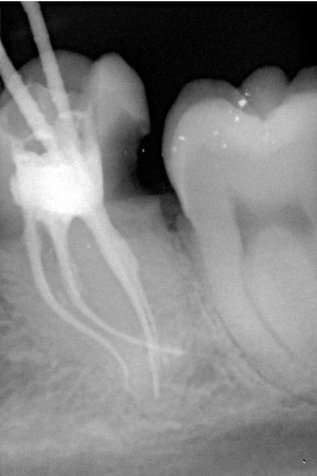

Da die Wurzelkanäle sehr klein sind und sich oft verzweigen, ist es nicht immer einfach, alle Kanäle mit ihren Seitenästen aufzufinden.

Bei der modernen endodontischen Behandlung können durch ein Dentalmikroskop auch kleinere Kanälchen aufbereitet werden, die man auch mit einer Lupenbrille nicht finden würde.

Nur wenn das Wurzelkanalsystem komplett aufgefunden und gereinigt wird, hat eine Wurzelkanalfüllung eine gute Langzeitprognose.

Aufsicht auf freigelegte Kanaleingänge mit Hilfe eines Dentalmikroskops bei geringer Vergrößerung

Durch eine bis zu 24-fache Vergrößerung sind die Kanäle besser darstellbar und dadurch auch effizienter zu reinigen. Durch Reste von Pulpagewebe im Wurzelkanalsystem kann eine Entzündung entstehen, mit der Folge einer erneut notwendigen Wurzelkanalbehandlung oder dem Zahnverlust.